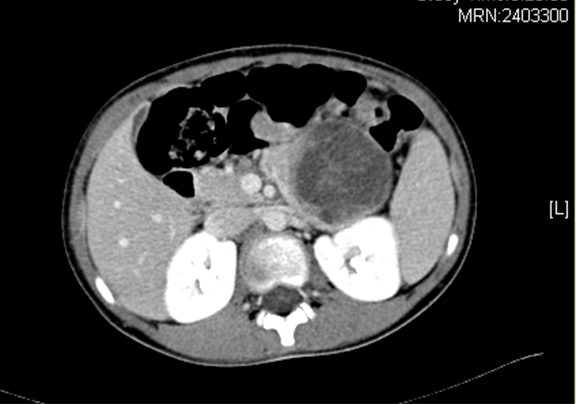

上腹部增强CT+三维:胰腺体尾部囊实性占位病变,考虑偏良性肿瘤可能性大,建议MR 进一步检查

术前CT检查:

动脉期

静脉期

平衡期